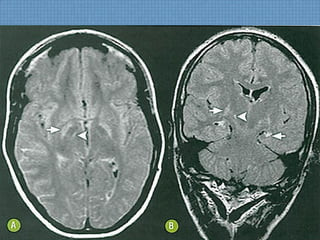

• Hipossinal em T1 e hiperssinal em T2/FLAIR na

porção medial dos tálamos, região periaquedutal e

corpos mamilares;

• Restrição à difusão nos tálamos;

• Impregnação por Gadolíneo em corpos mamilares

pode refletir desmielinização aguda.

EM NÃO ETILISTAS...

• Hiperssinal T2/FLAIR em núcleos bulbares de nervos

hipoglossos;

• Hiperssinal T2/FLAIR em núcleos pontinos dorsais de

abducente e facial;

• Acometimento difuso e multifocal do córtex cerebral,

• KORSAKOFF  ATROFIA DOS CORPOS

MAMILARES!